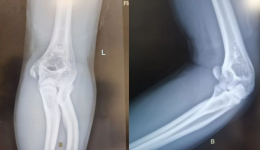

近日我院小儿骨科成功为一例严重错位的儿童肱骨外髁骨折患儿实施了超声辅助下无切口微创手术。患儿情况6岁8个月的患儿因摔伤致右肘部肿痛,活动受限2小时余来我院就诊。拍片显示右肱骨外髁骨折翻转错位(如图1),属最严重Song5型骨折。此类骨折保...